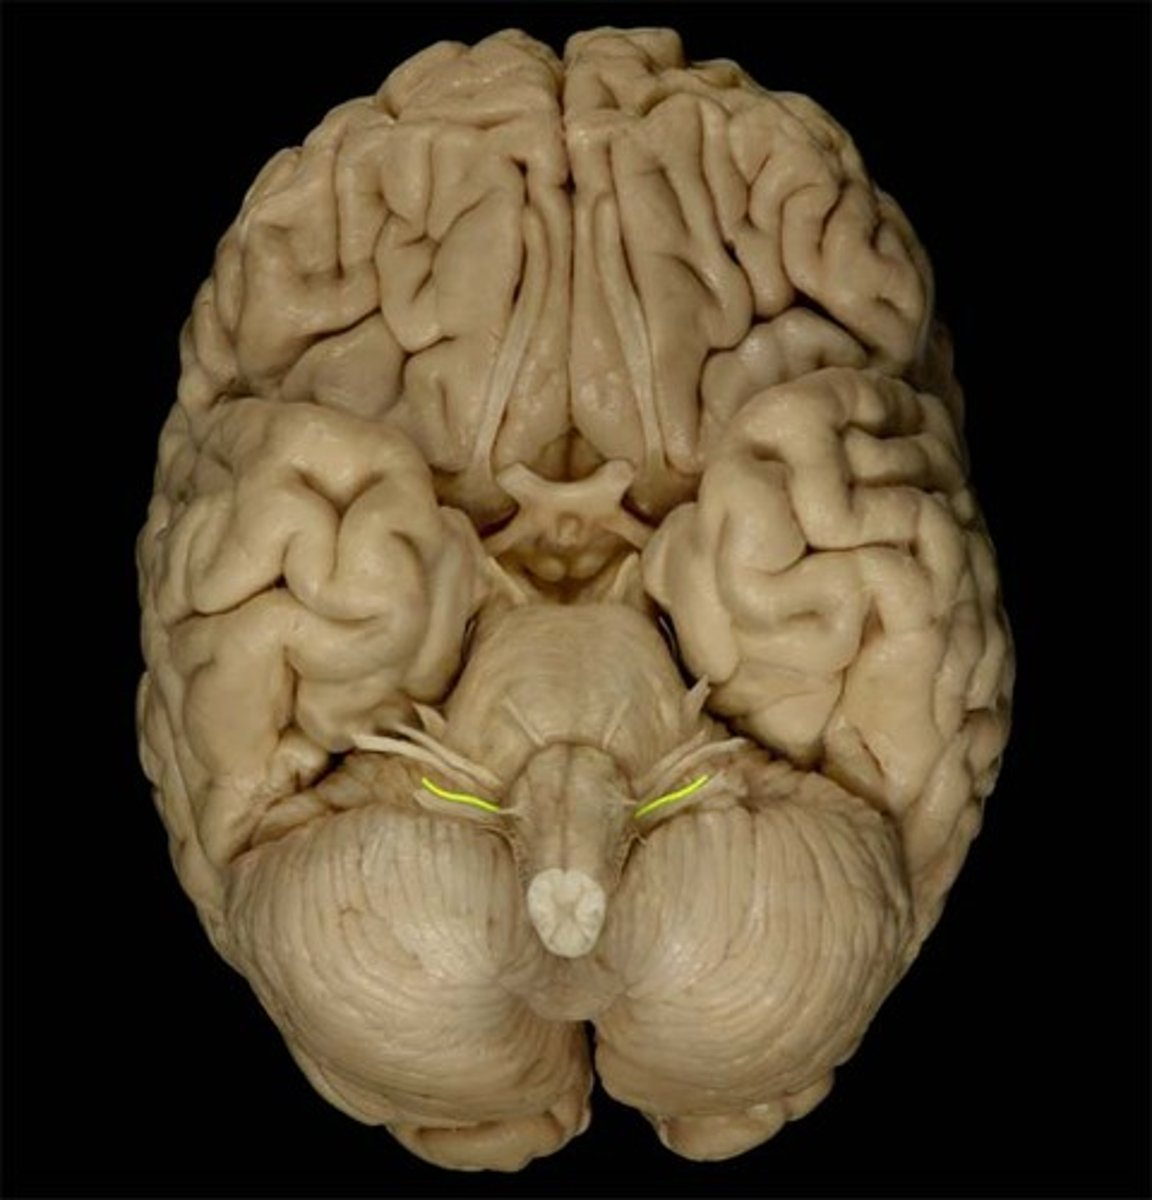

trochlear nerve (CN IV)

Motor cranial nerve that controls movement of the eye inferiorly and laterally; innervates superior oblique muscle